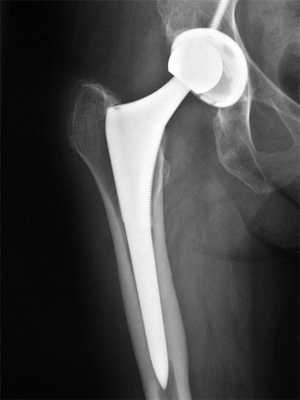

Протез для тотального эндопротезирования как правого, так и левого тазобедренного сустава является двухполюсным и состоит из следующих компонентов:

- чашка - устанавливается в предварительно обработанную вертлужную впадину;

- полиэтиленовый вкладыш - располагается между чашкой и головкой, необходим для обеспечения амортизации;

- головка - крепится на верхнем конусе ножки;

- ножка - имплантируется в костномозговой канал бедренной кости, который предварительно обрабатываются специальными фрезами (сверлами) и рашпилями.